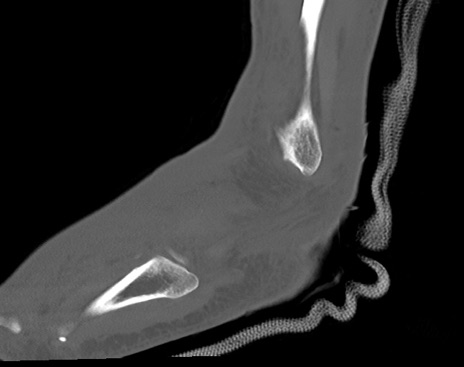

症例37 左足関節CT(矢状断像)

左足関節CT